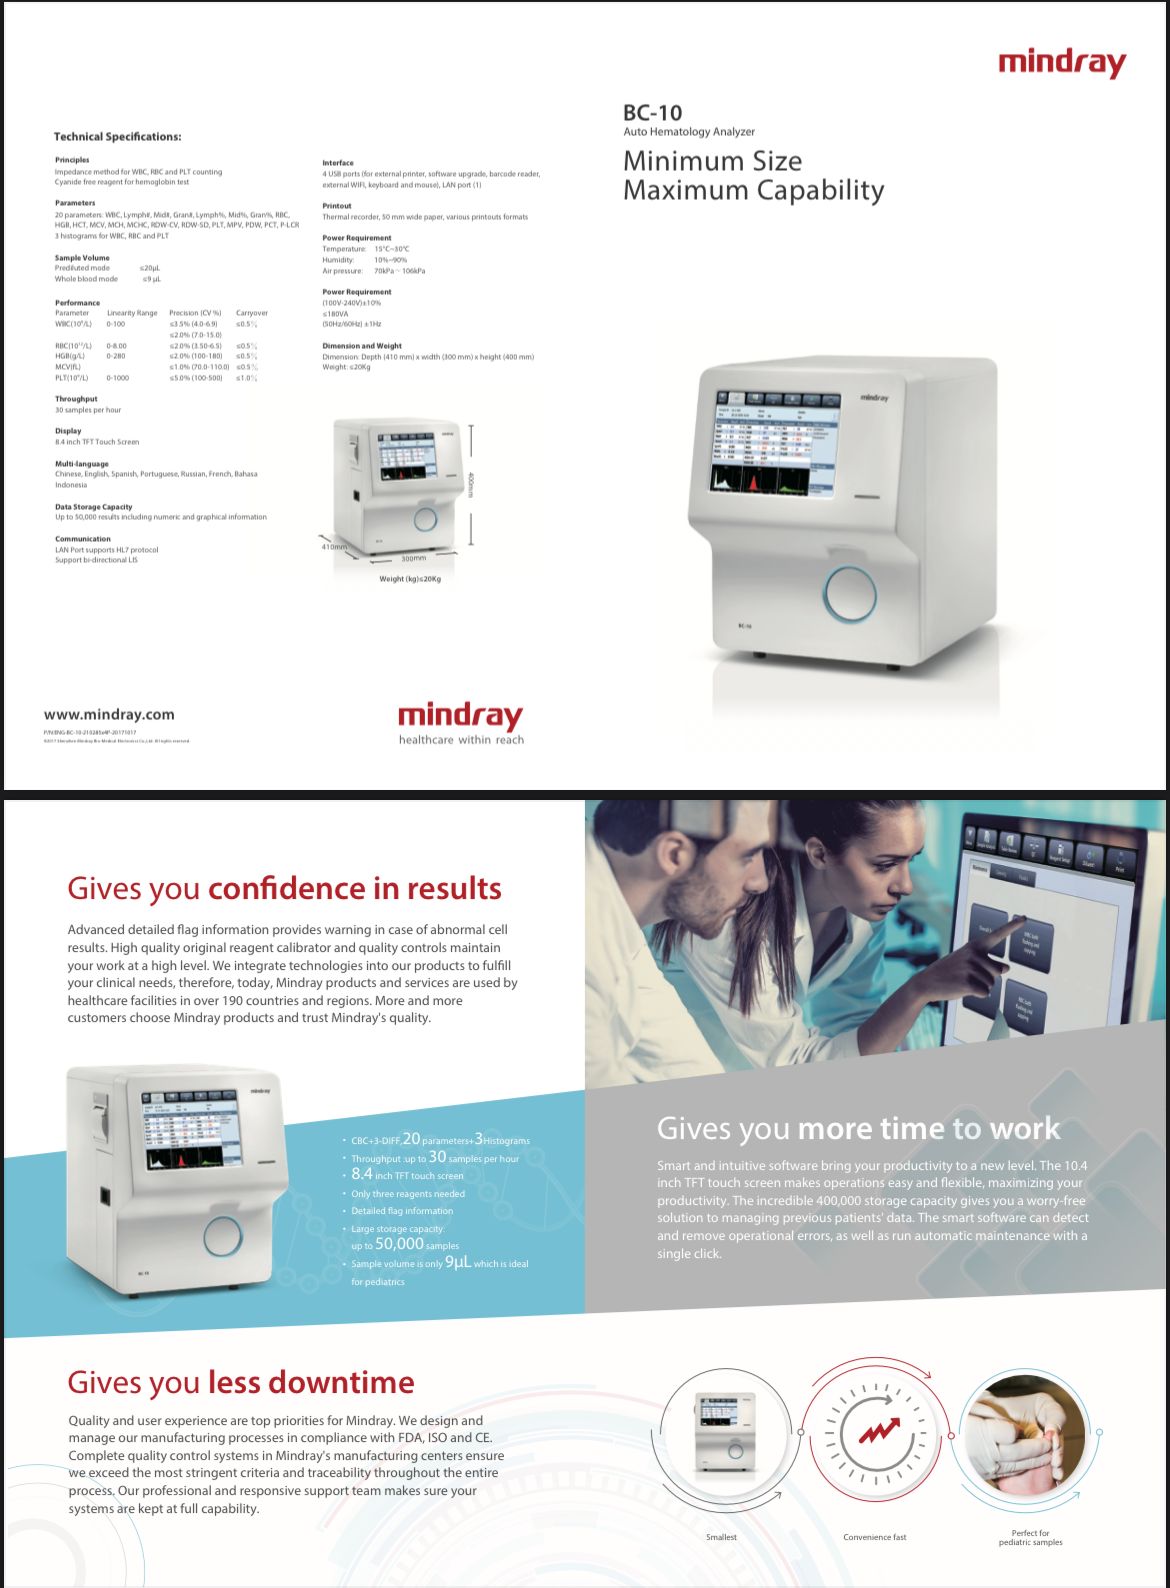

Auto Hematology Analyzer

Auto Hematology Analyzer

Auto Hematology Analyzer

Auto Hematology Analyzer

HEMATOLOGY ANALYZER

HEMATOLOGY ANALYZER

Automatic Hematology Analyzer

Automatic Hematology Analyzer